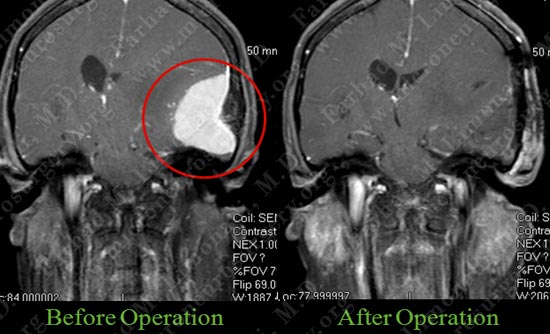

Tumor was removed in a gross total fashion.

Post op MRI shows complete resection of the tumor with no injury to surrounding neuro-vascular structures